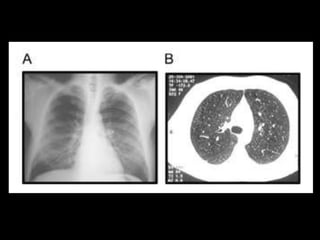

Tac de torax